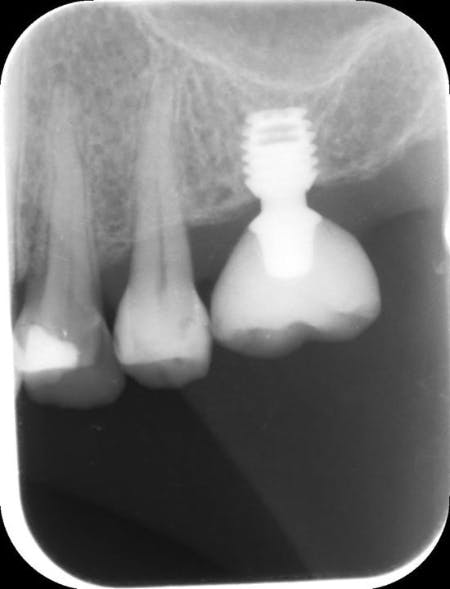

Qısa implantların sxematik və rentgenoloji görünüşü